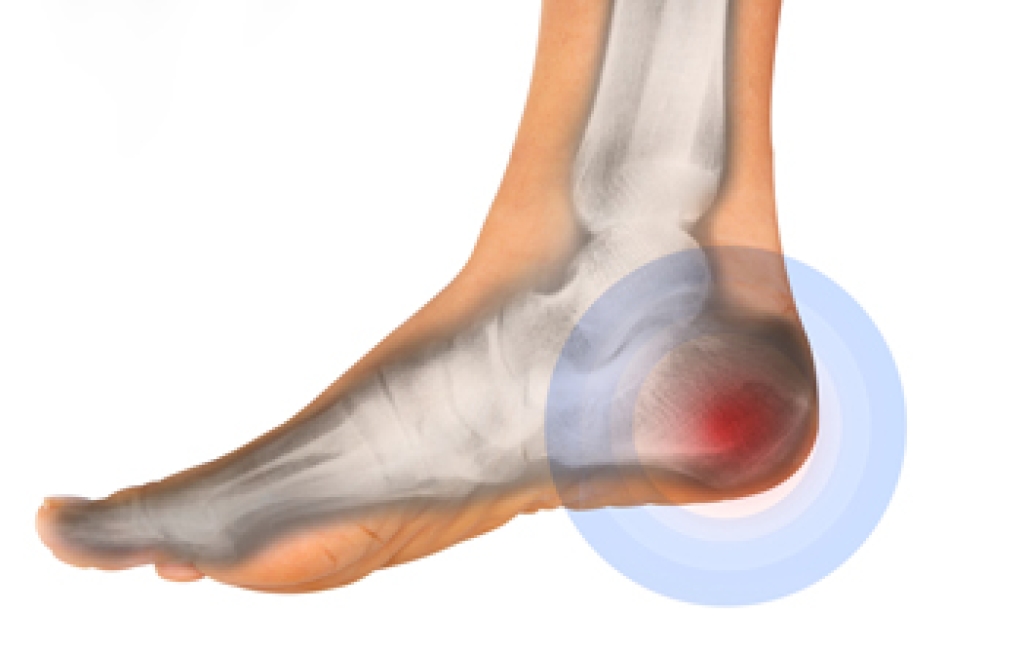

Vincent Vess, DPM is an experienced and compassionate podiatric physician and surgeon. He offers effective, non-surgical treatments for everything from heel pain, ingrown toenails, warts, and diabetic foot issues, to surgical procedures for bunion and hammertoe correction, tendon repairs, neuromas, joint issues, severe plantar fasciitis, sports injuries and more.